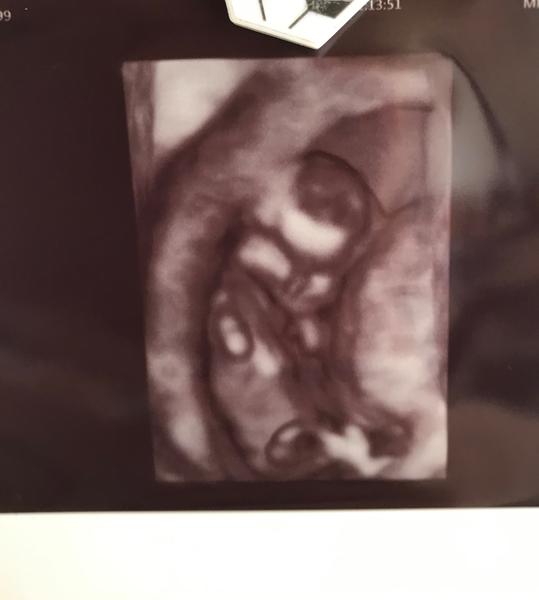

Dobrý den, jaké by jste řekli pohlaví podle hrbolku na fotce? Moc děkuji za názory.